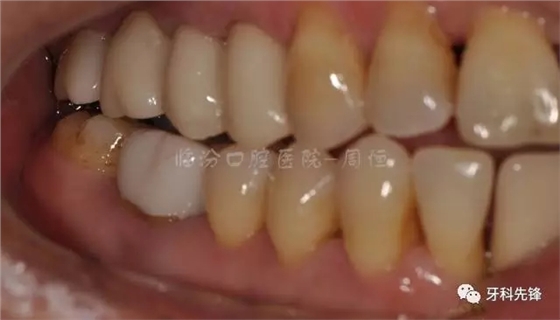

圖2 術(shù)前側(cè)位咬頜照